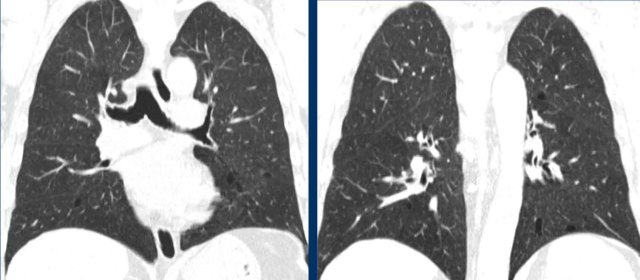

These are images of two different patients.

Although at first glance these images look similar, you may notice that on the left we have true cysts with a wall in a patient with advanced LCH, while on the right some appear to have a wall, but most of them do not.

This is centrilobular emphysema.